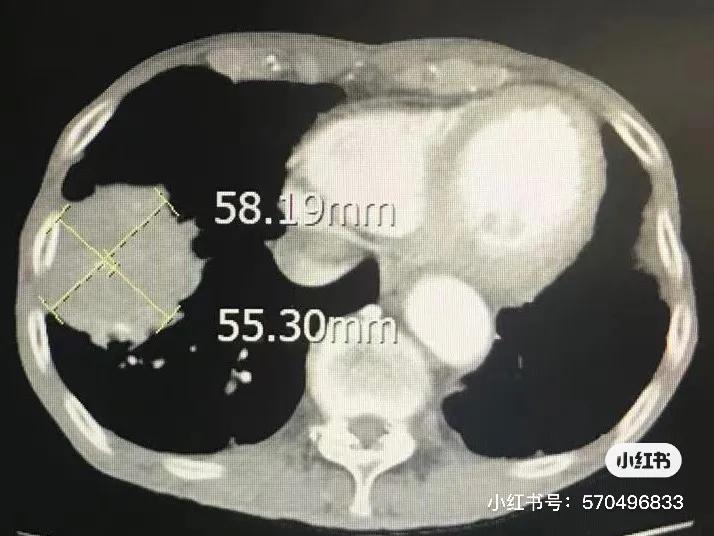

第一次冷冻后一个月CT